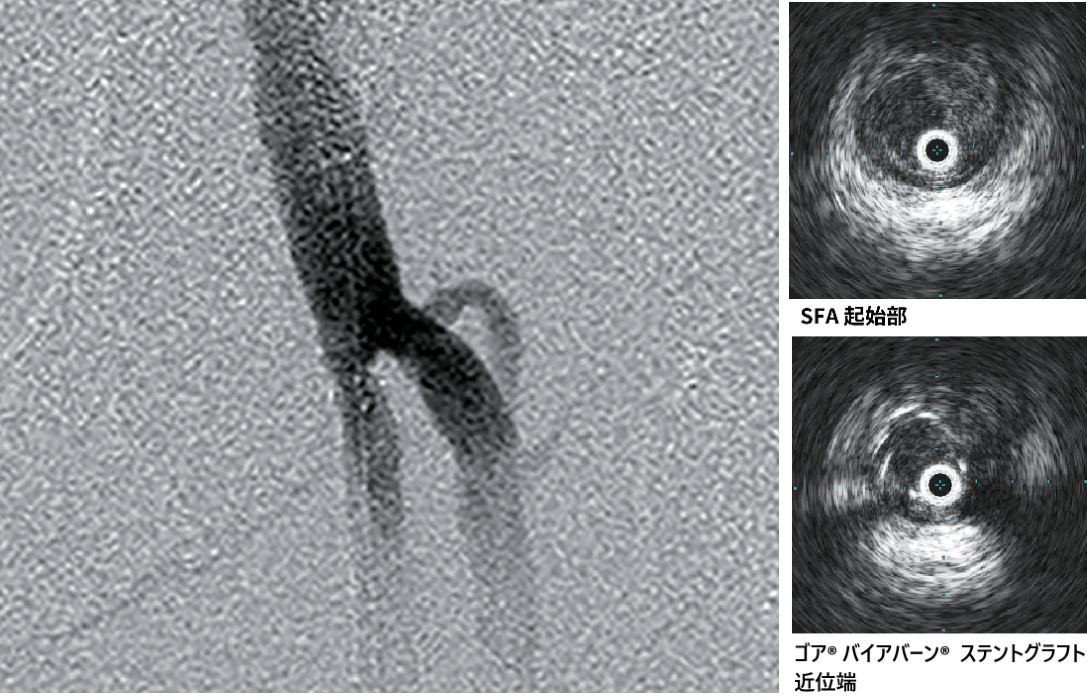

- 造影上は良好な血流改善を得られたが、IVUSではSFA起始部にプラーク残存を認めた(図3)。

- プラークをフルカバーするため、SFA起始部にバイアバーン® ステントグラフト径6.0/長50 mmを追加留置(図4)。

- 径6.0/長150 mm高圧バルーンにて高圧拡張を追加し、DFAの血流も問題がないことを確認して手技終了(図5)。